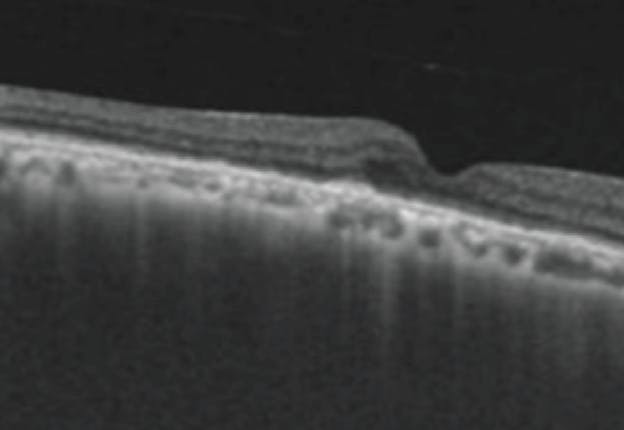

A 69-year-old man presented to the retina clinic with sudden onset loss of vision in the right eye for 1 month. Fundus examination revealed multiple small, hard drusen at the macula in each eye with subretinal hemorrhage at the fovea in the right eye. Swept-source OCT showed the presence of retinal thickening, subretinal hyperreflective material (SHRM)—including subretinal hyperereflective exudation and choroidal neovascular complex—subretinal fluid (SRF), and a shallow fibrovascular pigment epithelial detachment (PED) suggestive of type 2 choroidal neovascularization (CNV) (Figure 1A). OCT angiography (OCTA) of the right eye showed a neovascular net in the outer retina and choriocapillaris.

<p>Figure 1. The patient’s OCT shows the presence of type 2 CNV and SHRM (A). After two intravitreal injections of ranibizumab and one of IVZ, OCT showed persistent SHRM (B).</p>

Figure 1. The patient’s OCT shows the presence of type 2 CNV and SHRM (A). After two intravitreal injections of ranibizumab and one of IVZ, OCT showed persistent SHRM (B).

The patient received two intravitreal injections of ranibizumab 0.5 mg/0.05 mL (Lucentis, Genentech) at baseline and at 1 month, along with one intravitreal injection of ziv-aflibercept 1.25 mg/0.05 mL (IVZ; Zaltrap, Sanofi) at the end of the second month.

At the 3-month follow-up visit, OCT imaging showed a minimum reduction of the SRF with the persistence of SHRM (Figure 1B).